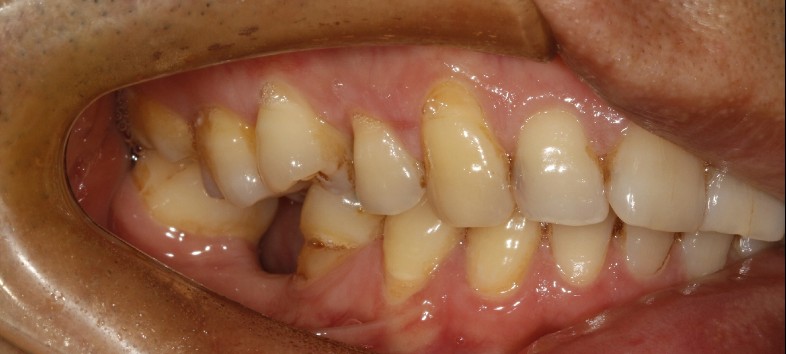

患者男,四十四岁,36,46缺失已植入种植体,附着龈不足,缺牙区牙槽嵴呈刀刃状,缺牙区咬合间隙及近远中间隙尚可。可行游离牙龈移植术增宽种植体周围附着龈的面积。